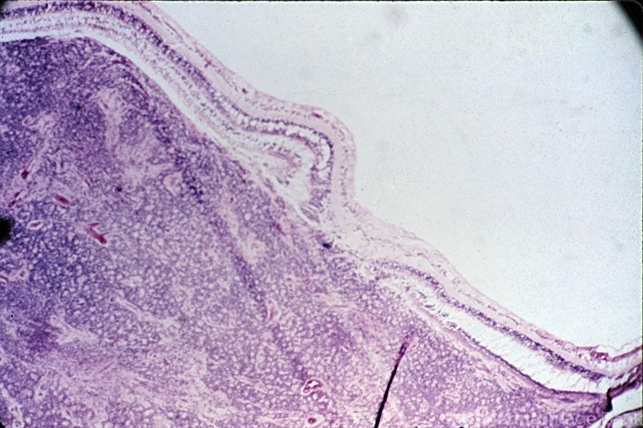

- Low-power view of an undifferentiated retinoblastoma underlying the macular area ( x25).